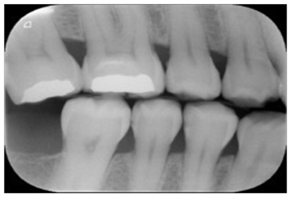

| Type | Publication Used | Variable Measured | Sample Image | Features |

|---|---|---|---|---|

| Bitewing X-rays | [37,49,54,77,84,85,86] | Caries detection (posterior initial proximal caries) | ![]() | Accuracy |

| Periapical X-rays | [12,39,40,59,86,87,88,89,90,91,92,93] | Diagnosing invisible proximal dental caries | ![]() | Display the entire tooth, from the crown to the root, where it connects to the jaw. |